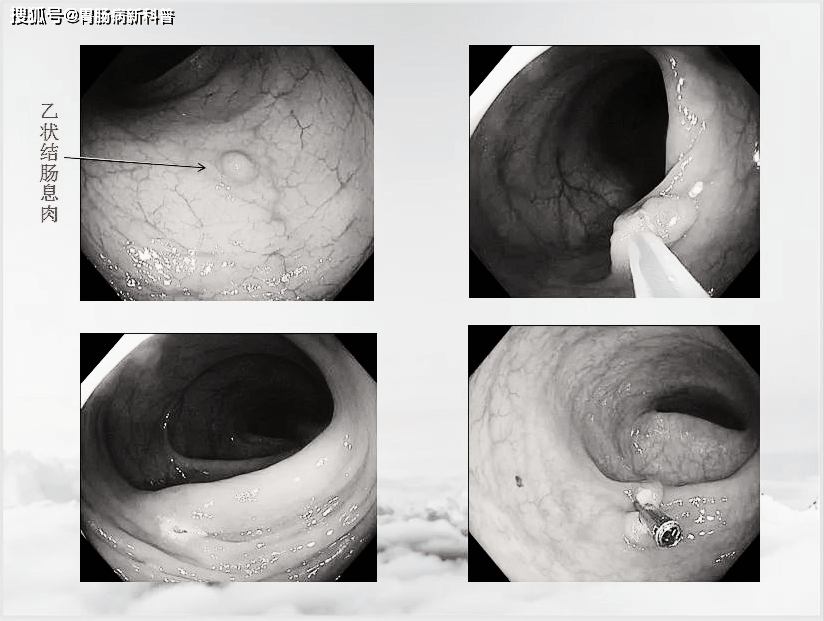

吴女士,41岁,平素排便正常,无诉不适,元月1日规体检中行无痛胃肠镜检查时,在乙状结肠发现数枚息肉,当即予以切除,术后的病理显示,其中一个为管状腺瘤伴腺体低级别上皮内瘤变,2个是高级别上皮内瘤变(伴少量粘膜内腺癌)。

2021年元旦节,46岁的赵女士是比较幸运的一个。

46岁的赵女士,趁着元旦放假,预约了胃肠镜体检。发现一个大约2公分的息肉,当即给予摘除,阻断了癌变之路,经病理证实为癌前疾病——绒毛状腺瘤(其恶变率约为40%)。

凸起处为肠息肉

12月31日,还有一例51岁男性,无明显症状,仅仅是长期大便不成形来做检查。

发现距肛门10cm处一凹陷性息肉,当即予以内镜下EMR切除,昨天,病理证实为中分化腺癌。

直肠息肉样隆起

病理报告为腺癌

像这两例病例,因为发现的早,不用开刀,只需要在肠镜下就可以顺利切除病变,费用非常低廉,不需要化疗,也不需要吃药,只需要定期复查即可。